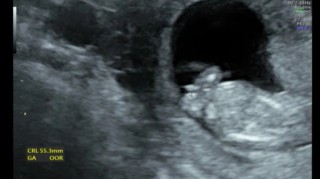

写真:12w1d:りぷとんさん

2022年9月 12w1d 7.5cm

高齢出産なので、NIPT(出生前診断)と胎児ドッグを受けてきました。

小さい手や足を一生懸命動かしていて本当に可愛かった!辛いつわりも吹っ飛びます。もう膀胱でおしっこもちゃんと作られていたり、この段階で分かってしまうのがすごい!9年前の一人目の時よりレベルが上がっていて終始驚いてました笑

12w1d BPD22mm

4日ほど大きく、心拍も鼻の骨や指や大腿骨もしっかりしてピョコピョコ動いてた!もう愛しい!!まだつわりはあるけどお母さんも頑張るよ♪